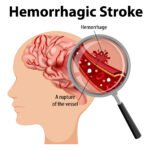

- Stroke